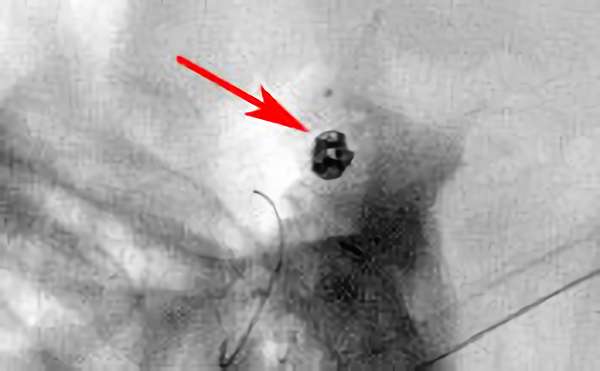

No.1628 手術中